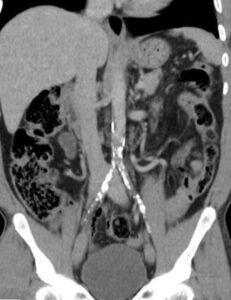

🔹 شواهد تصویری

در نمونههای ارائهشده، دو مورد از بیماران با پلاکهای ظاهراً گسترده در سیتیاسکن بررسی شدند.

اما پس از انجام آنژیوگرافی عروقی، مشخص گردید که:

-

لومن واقعی عروق بهطور قابل ملاحظهای باز است،

-

میزان انسداد کمتر از آن چیزی است که در سیتی دیده میشود،

-

و تصمیمگیری جراحی بر اساس یافتههای واقعی میتواند با اطمینان بیشتری انجام گیرد.

این موارد نمونهای از تفاوت بین برداشت تصویری ناشی از Blooming Artefact و واقعیت آناتومیک هستند.